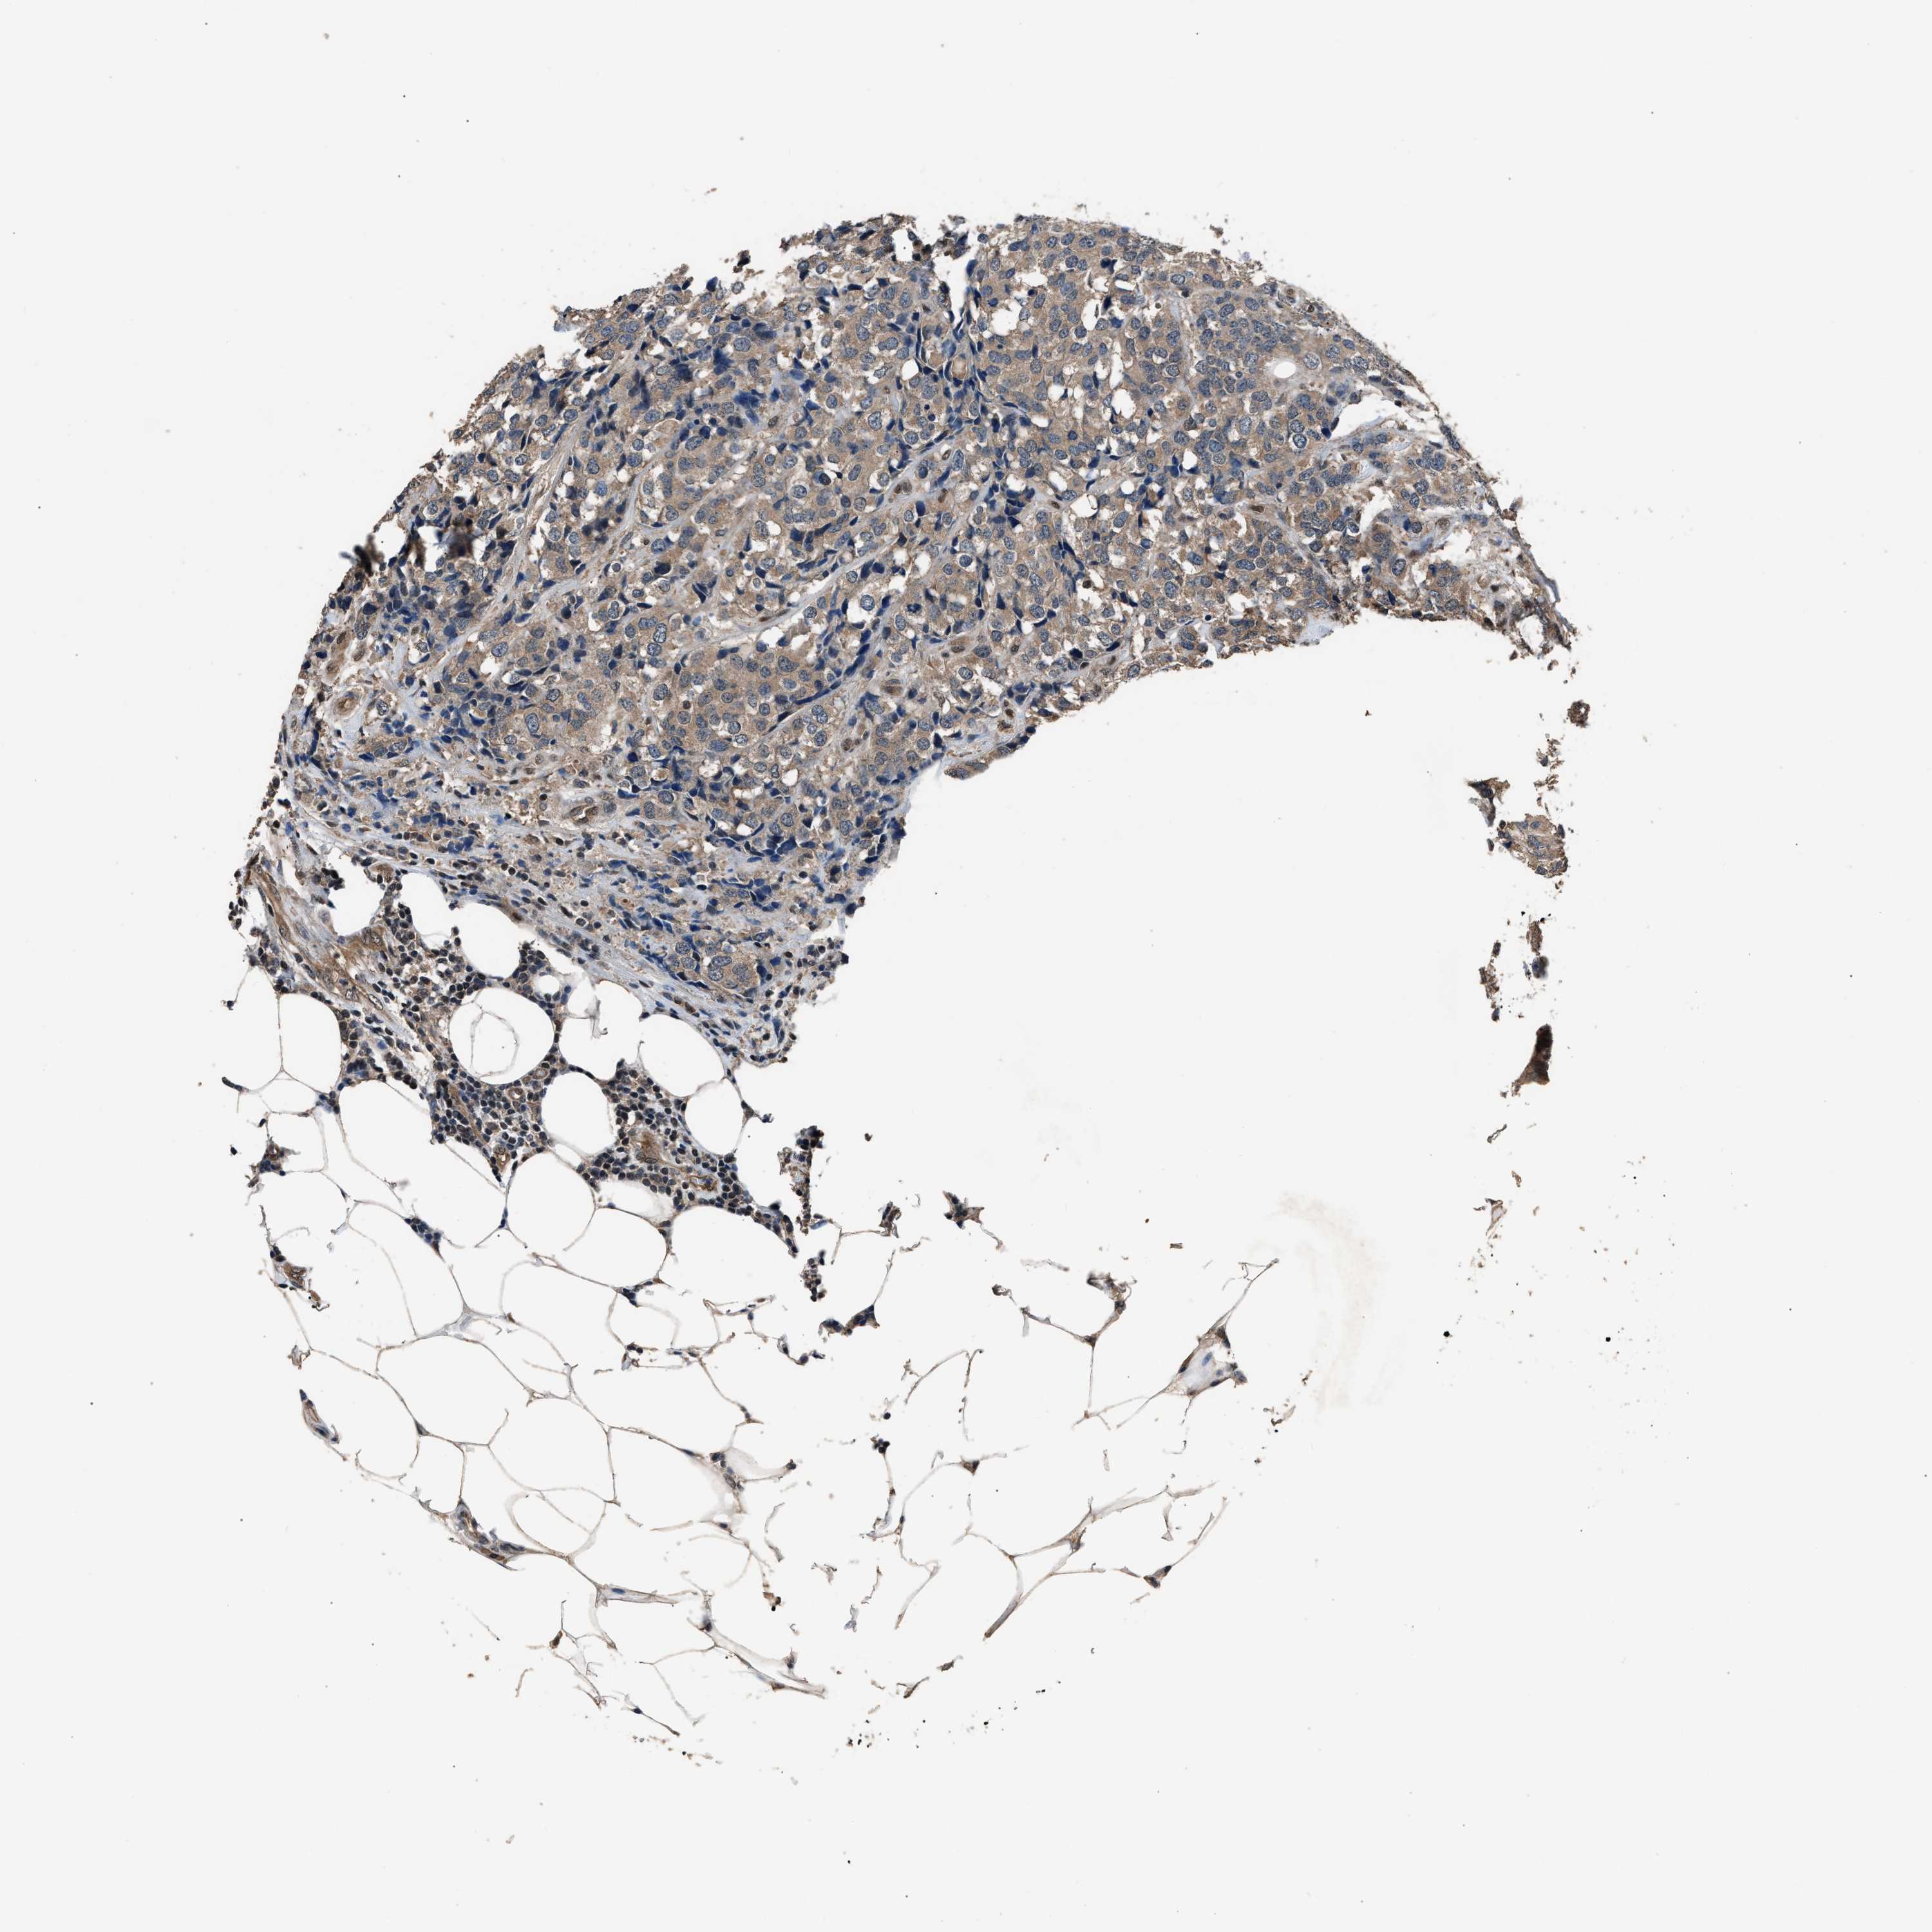

CANCER BREAST CANCER Show tissue menu

BRCA TCGA BRCA VALIDATION PROTEIN EXPRESSION